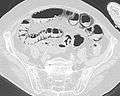

Pneumatosis intestinalis in computed tomography with intestinal ischemia. Lung window for better representation of the gas deposits in the intestinal walls.- Upright AP radiograph showing gas in the wall of the small bowel in the left upper quadrant indicative of pneumatosis intestinalis.

- Coronal reformatted MDCT image showing extensive pneumatosis intestinalis in the left upper quadrant small bowel. The pneumatosis is more cystic and nodular in the small bowel in the midline and the right of midline. This patient had a relatively benign presentation without bowel ischemia and was treated conservatively.